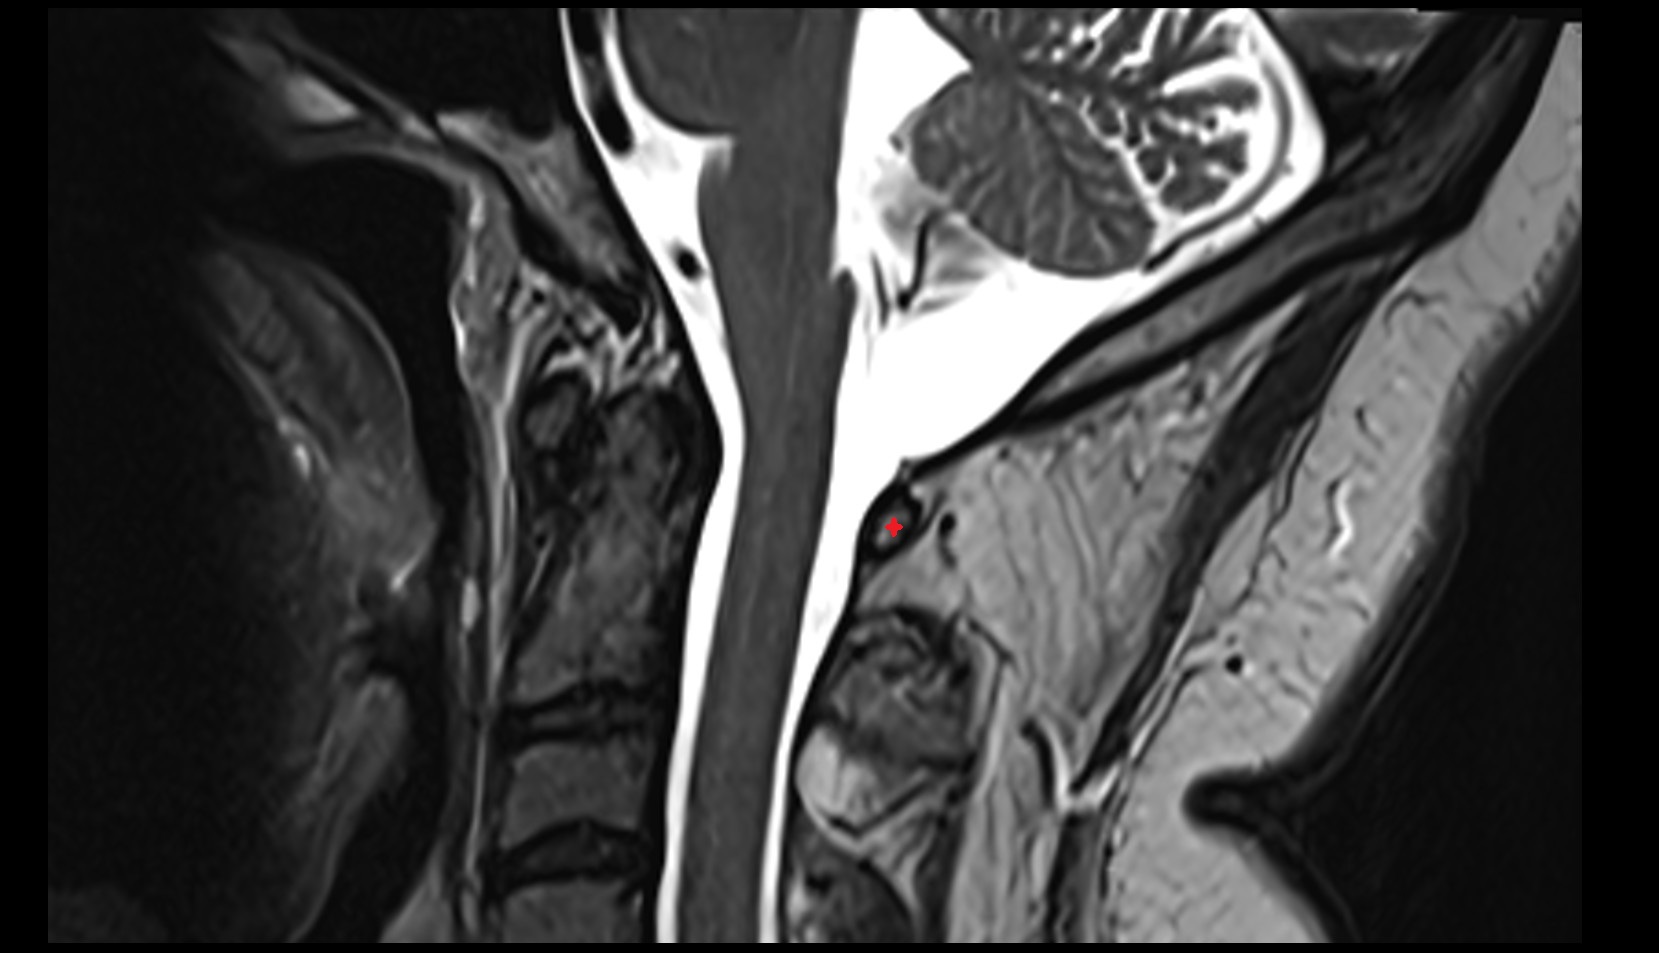

- Uterus

- Cervix of uterus

- Vagina

- Rectum

- Urinary bladder

- Vesicouterine pouch

- Rectouterine pouch (pouch of Douglas)